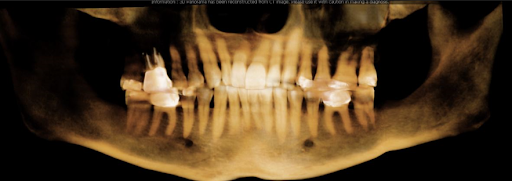

How is dental cavitation diagnosed?

Dental cavitation will be diagnosed with 3D Cone beam Scan plus experienced radiologist and surgeon/holistic dentist. The scan is the only tool that properly helps to observe changes in the bone density fluctuations, tissue changes, and adjacent anomalies cross-sectionally millimeter by millimeter of the infected area. It is important that the procedure is performed by an experienced holistic dentist.